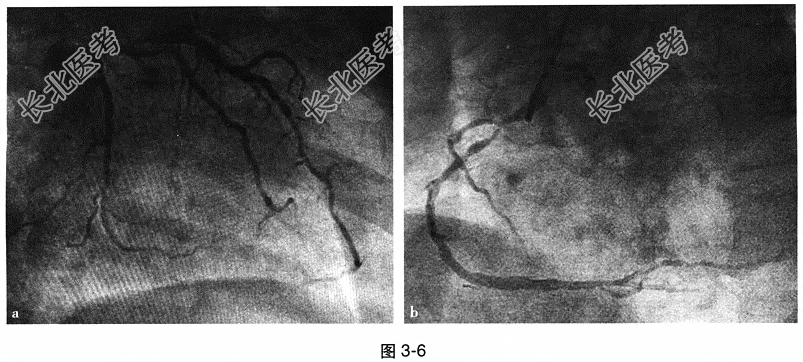

- 多项选择题4.[提示]冠状动脉造影:左主干(LM)体部狭窄30%; 前降支(LAD)近段弥漫病变,发出D1后狭窄80%, 中段狭窄75%,远段狭窄60%~70%; 回旋支(LCX)近段狭窄60%;右冠状动脉(RCA)开口异常, 近段狭窄95%,中段狭窄80%, 远段狭窄30%~40%,见图3-6。于RCA近中段置入支架1枚, 于LAD近段狭窄处置入支架1枚,并静脉泵入替罗非班强化抗血小板治疗。术后3小时患者突然意识丧失, 心电监护示室速,颈动脉搏动触不到。